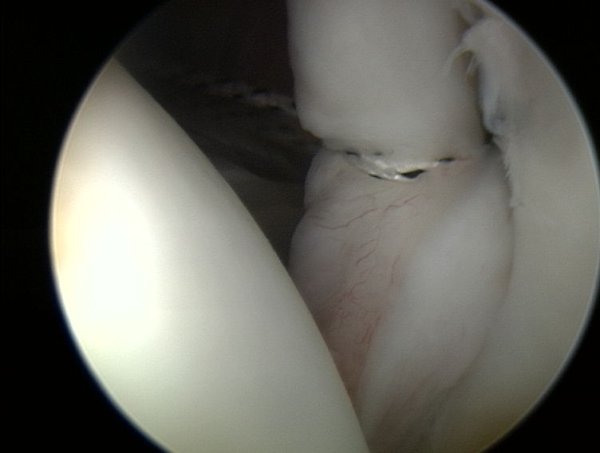

Tutaj widoczny jest obrąbek stawowy z panewką ( patrzymy od tyłu na przednią cześć panewki) bez zmian, z lewej główka kości ramiennej.

Z prawej strony jest widoczny brak obrąbka stawowego na panewce, jedynie w górnej cześci jest jeszcze rozpoznawalny. Z lewej strony widoczna jest głowa kości ramiennej.